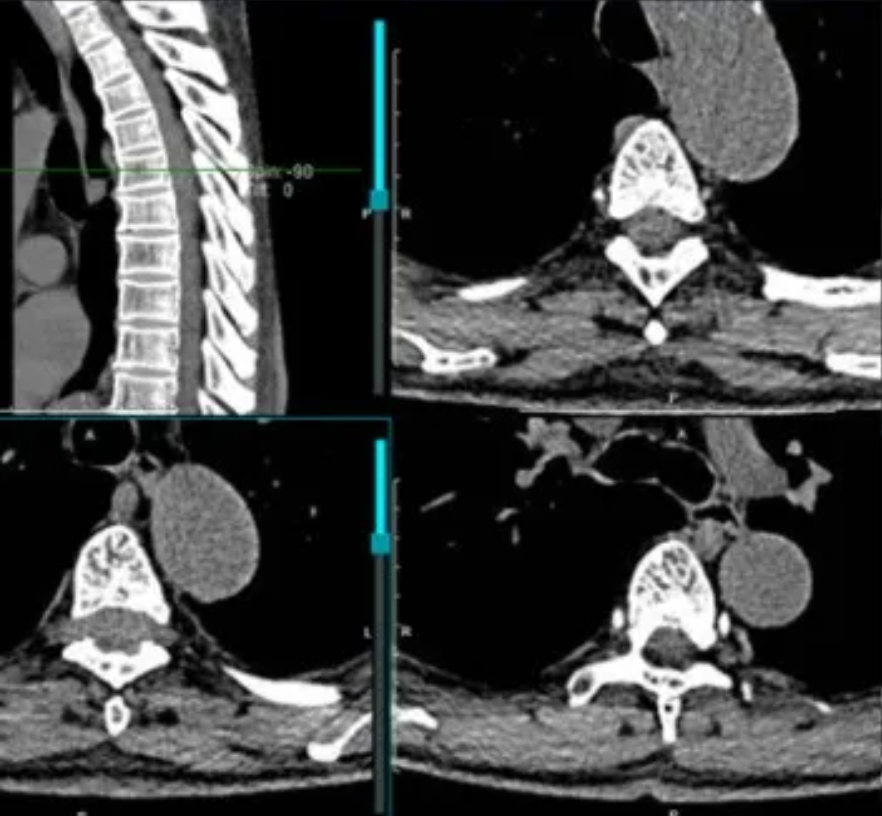

患者男性,74岁,退休在家,1月前无明显诱因突发上背部疼痛,起始为隐痛,后出现双下肢无力(肌力3级+),双下肢针刺感,走路踩棉花感。无恶心、呕吐,无头晕头痛。于当地医院就诊,行CT,MRI示颈胸段(T4-T6)椎管内占位。

CT:T4-6椎管内硬膜囊结构消失伴软组织密度增高,向相应双侧神经孔延伸,相应骨性椎管未见破坏。

MRI:T4-6后方偏左侧见椎管内髓外异常信号影,T2WI呈高信号,大小约8*9mm,上下径约50mm,相应节段脊髓受压。